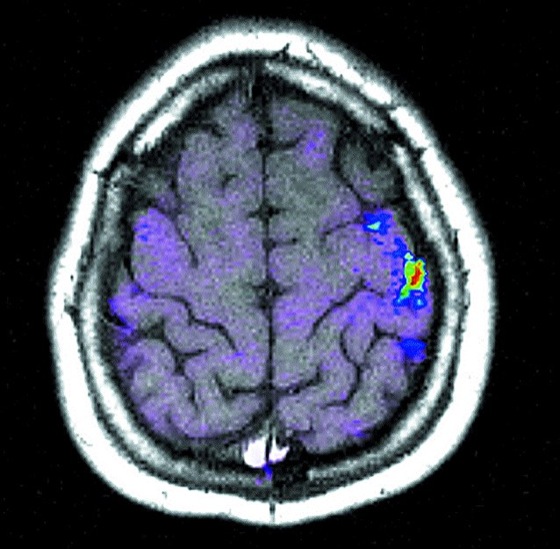

Bei allen Schritten einer NMR-Bildgebungssequenz können Bildartefakte entstehen. Die wichtigsten sind Partialvolumen-Effekte (›Verschmieren‹ des Bildes bzw. Überlagerung verschiedener Strukturen bei Variationen der Probenstruktur innerhalb der angeregten Schicht), chemische Verschiebungsartefakte (vor allem beim Lesegradienten, siehe Abb. 4) und Flußartefakte (beim Phasengradienten). Kompliziertere Artefakte können durch das Zusammenspiel von Diffusion und lokalen Suszeptibilitätsunterschieden in der Probe entstehen (NMR-Diffusions- und Bewegungseffekte).Anwendungsgebiete: Die bekannteste Anwendung der NMR-Bildgebung liegt in der medizinischen Diagnostik (siehe Abb. 5 und Abb. 6, Kernspintomograph). Daneben wird sie jedoch auch zunehmend in der biologischen Grundlagenforschung sowie für die Untersuchung von Proben aus den Materialwissenschaften, der chemischen Prozeßtechnik und der Lebensmitteltechnologie angewandt. Die speziellen Vorteile der Kernspintomographie für alle diese Bereiche sind vor allem die Zerstörungsfreiheit sowie die Vielfalt an möglichen Kontrastparametern, die mit ein und derselben Methode untersucht werden können.

Kernspintomographie 6: Funktionelle NMR-Bildgebung am menschlichen Gehirn: Dem anatomischen Bild überlagert ist die Signaländerung durch die neuronale Aktivität bei der Ausführung einer Handbewegung. Die Aktivität ist im Motorcortex konzentriert.